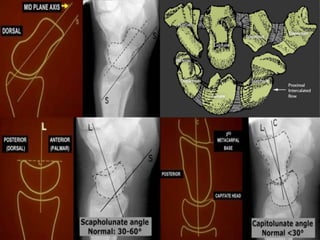

A simple approach is to consider the lunate

which is usually the easiest carpal bone to

visualize on a lateral wrist image. If the

lunate is abnormally tilted in a dorsal

direction on a standard lateral wrist image,

a DISI should be considered. If the lunate is

abnormally tilted in a volar direction a VISI

should be considered. DISI is due to

disruption of the scapho-lunate articulation.

VISI is secondary to disruption of the luno-

triquetral articulation.

DISI deformity.

DISI.

Volar intercalated segmental instability(VISI).